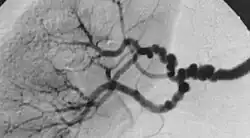

Wszystkie trzy typy mogą występować samodzielnie albo łącznie u jednego pacjenta. Klasyfikacja angiograficzna wyróżnia typ wieloogniskowy (multifocal type), z licznymi zwężeniami i obrazem „sznura pereł”, któremu w klasyfikacji histologicznej odpowiada typ z zajęciem błony wewnętrznej, typ cewkowy i typ ogniskowy, nie pokrywające się z klasyfikacją histologiczną.

| Klasyfikacja angiograficzna FMD | |||

|---|---|---|---|

| Typ I | Typ wieloogniskowy (multifocal type) | 62%[15] | ![]() |

| Typ II | Typ cewkowy (tubular type) | 14%[15] | ![]() |

| Typ III | Typ ogniskowy (focal type) | 7%[15] | ![]() |